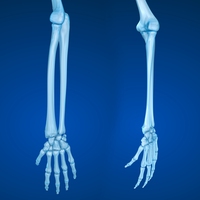

radius

one of the bones found in the lower arm

ulna

humerus

upper arm bone